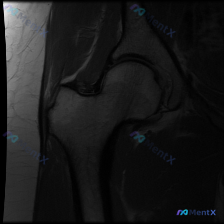

看到一个髋关节MRI病例,单幅冠状位T2加权像显示髋臼外上缘盂唇有局灶性高信号改变。正常情况下,盂唇在T2加权像上应该是低信号的。大家看看这个高信号更可能是盂唇撕裂还是退变?还需要补充哪些序列的图像来明确诊断?

看到一份髋关节MRI分析材料,患者临床怀疑盂唇病变,但单幅冠状位T2序列显示: - 髋关节解剖结构完整,骨髓信号均匀 - 关节间隙清晰,软骨轮廓连续 - 髋臼盂唇未见明显形态异常或高信号撕裂影 - 关节周围软组织无明显水肿、萎缩或积液 这种影像阴性但临床高度怀疑的矛盾,大家怎么看?单张T2像能完全排...